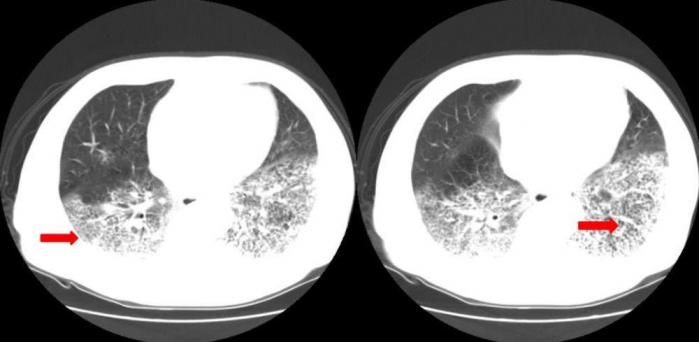

国内这边,2020 年疫情刚爆发那会,有患者在医院照 CT 的时候已经明显双肺病变,有磨玻璃状阴影。但硬是核酸检测 6 次依然是阴性。

有关专家也曾表示,CT 结果非常符合新冠肺炎但核酸检测却为阴性的病例大约占 30-40%。